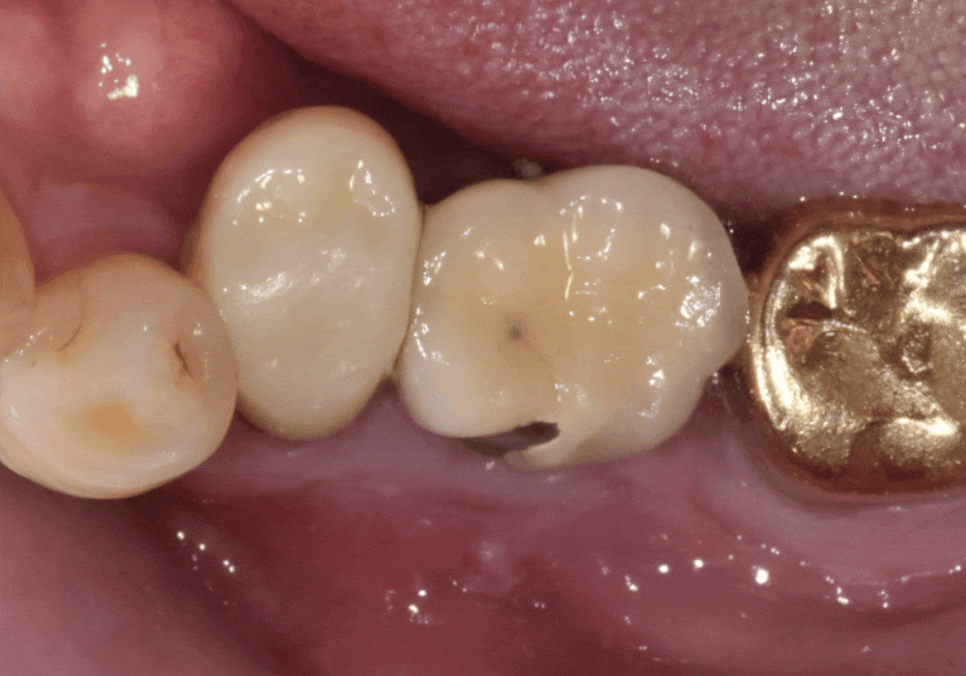

입안을 살펴보니

임플란트 바로 앞 치아(#35)가

많이 흔들리는 상황이었고,

잇몸도 부어있는 모습을 확인할 수 있었어요,